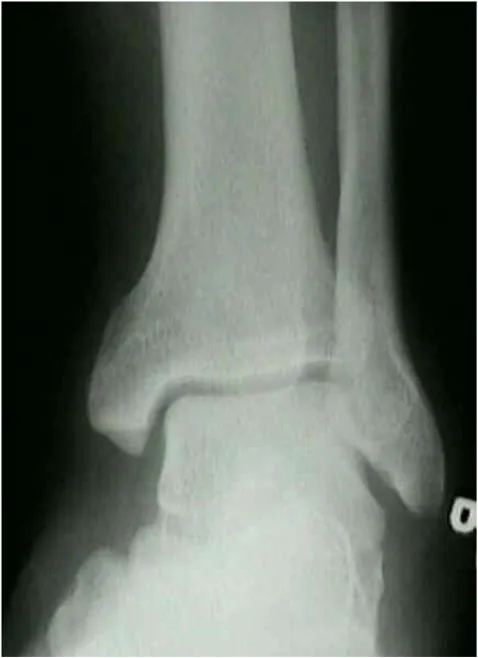

A. AP view

Identifies fractures of

malleoli

distal tibia/fibula

plafond

talar dome

body and lateral process of talus

calcaneous